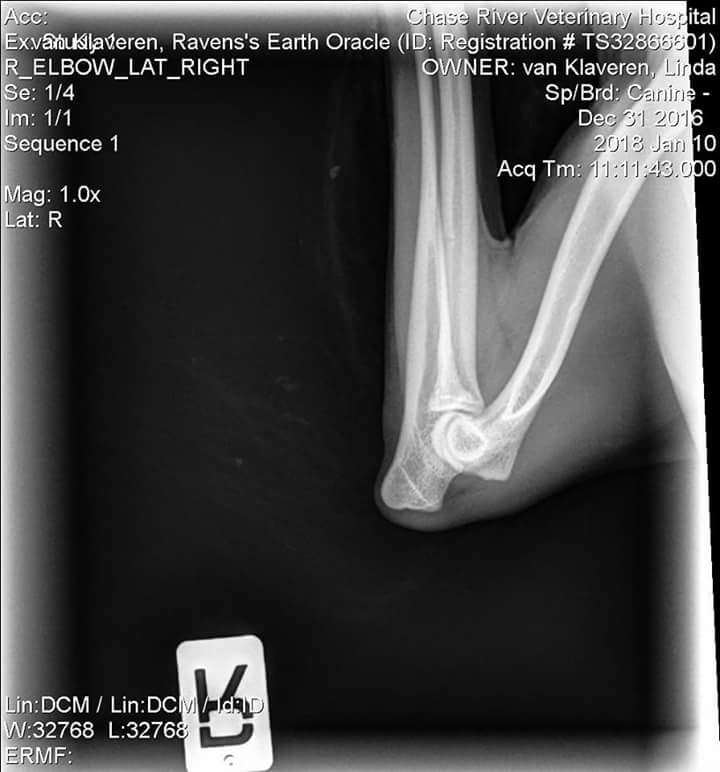

OFA Test Results:

Test Date - Jan. 10, 2018

Report Date - Jan. 15, 2018

· ELBOW PRELIMINARY NORMAL